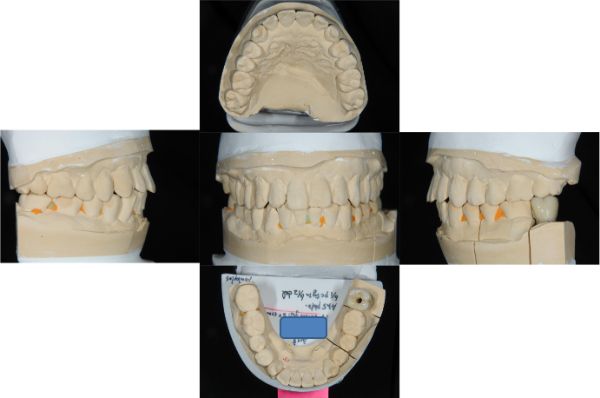

上咬合器製作模型

咬合器製作假牙